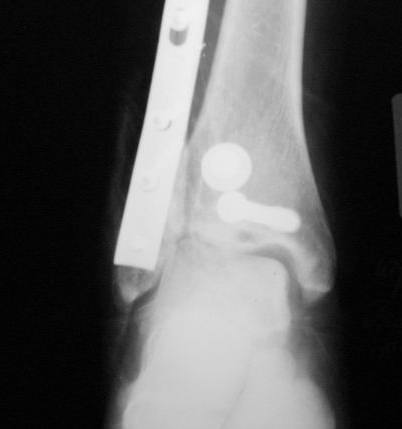

Уважаемые коллеги! Как и обещал, представляю плоды своей работы. Хвалиться особо нечем. Пошли задним

доступом сначала к м/берцовой кости, благодаря смещению линию перелома удалось сразу дифференцировать и по ней узким долотом (без молотка) мобилизовали отломки. Затем выделили задний край, там было проще пройти по линии перелома. Далее пластина по задней поверхности в дистальный отломок, винт проксимальнее пластины и дистрактором с трудом растянули отломки, ощущение было идеальной репозиции м/берцовой кости( доступен осмотр по задней и наружной поверхности), далее винты стандартно. Кстати, положение больной на боку: очень неудобно, но по-другому потом не повернуть на спину, чтобы сделать снимки в стандартных проекциях (ЭОПа нет). Затем дистрактор (два полукольца, спицы), репозиция заднего края, спонгиозный винт с шайбой, слишком проксимально, поэтому + еще один. Доступ к дельтовидной связке: рубец в передней порции, частично иссечен, шов. В общем, длительность операции 3,5 часа, а сказать, что все задуманное получилось, не могу.

Все таки нужно было стянуть ДМС. Судя по снимкам остался подвывих.